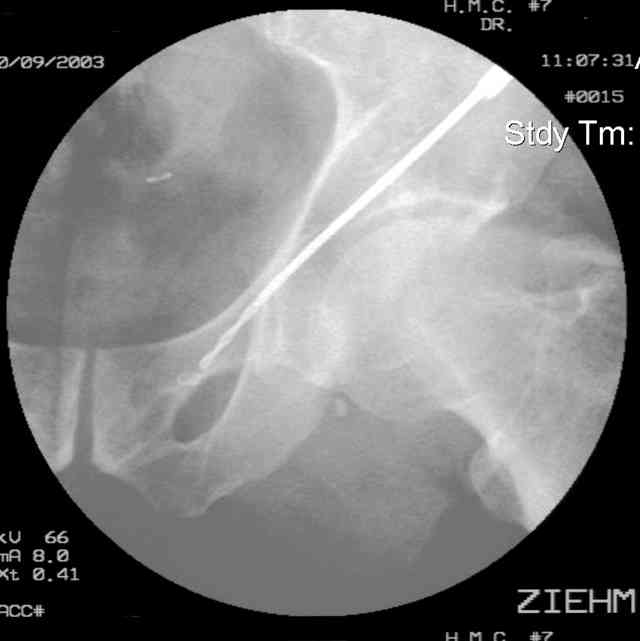

Prone Inlet

OK, now we're inserting the drill percutaneosuy using a sleeve. This fluoro shot is not for this patient (notice no clamp) but I was too lazy to go searching the PACS for one with the clamp on, so pretend...I'll save the next ones and send along...the imaging is the same and the clamp doesn't obstruct imaging other than very rarely...you can always tilt the C-arm a bit to clear it if the clamp obstructs the exact spot that you'd like to see. We'll assume that everyone knows the safe zone for a medullary ramus screw. Use a calibrated drill and sleeve of known length to simplify your life...or use Alex's fancy cannulated screws...I like 3.5mm screws because the oscillating 2.5mm drill bounces and remains intraosseus when it oscillates and contacts endosteal cortical ramus... so will the screw, and like a long bent screw IF the fracture is clamped... if unclamped, when the screw contacts the endosteum, it pushes the reduction apart instead of bouncing. The big 7mm cannulated screws fit few patients and extrude...we very rarely use them any more...you'll see an old one later.